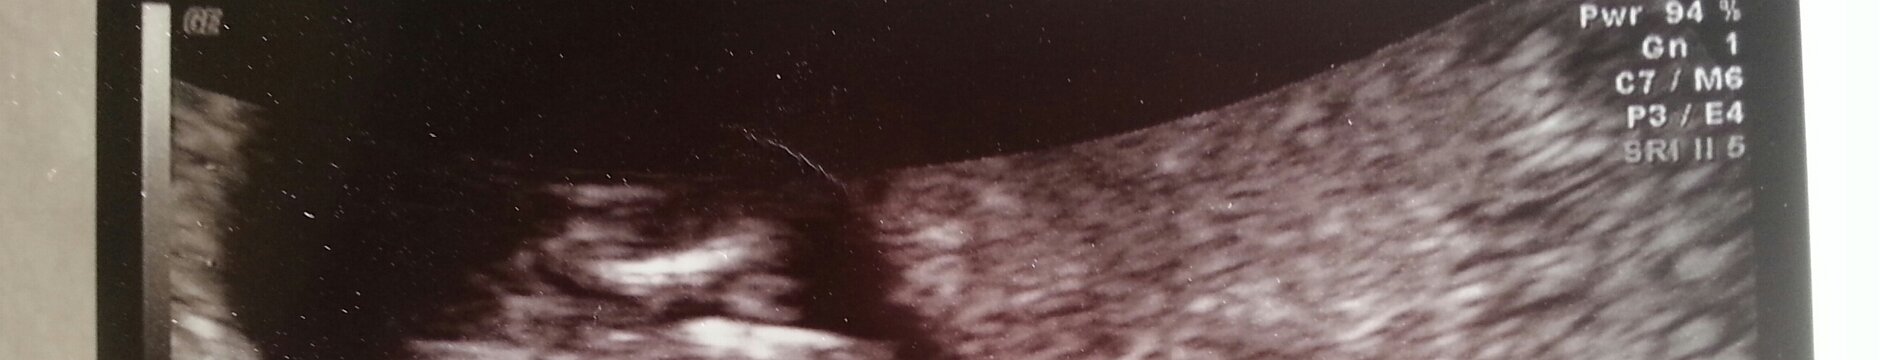

Our Baby